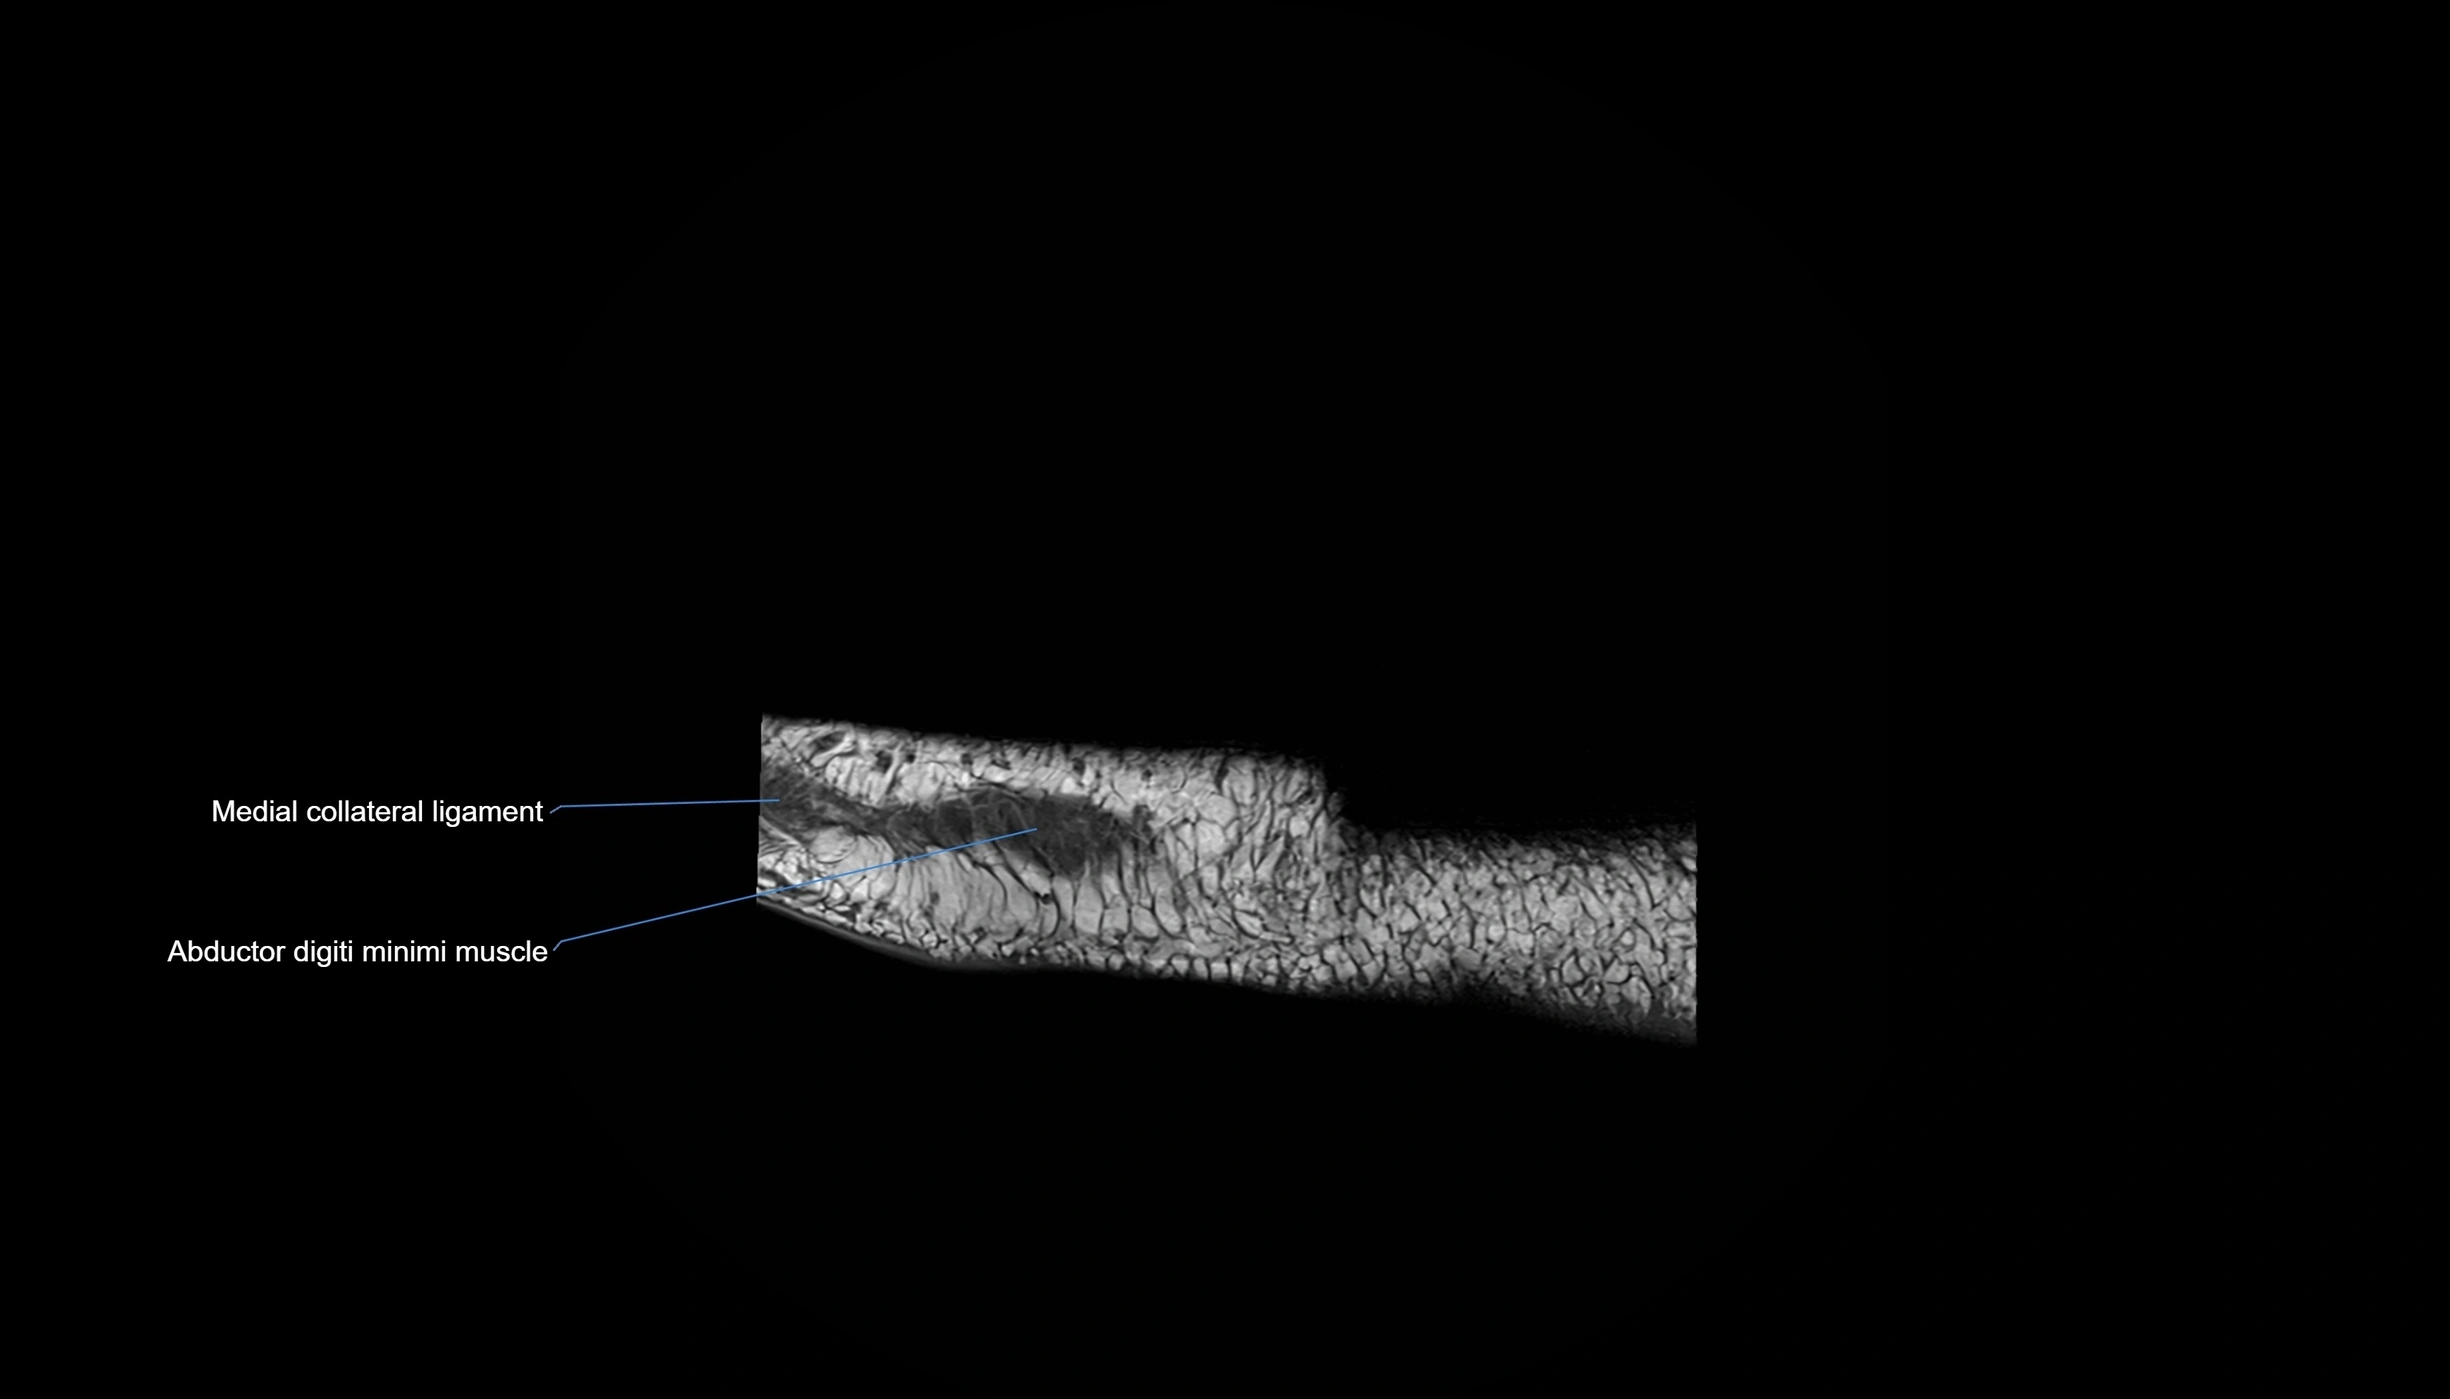

MRI image